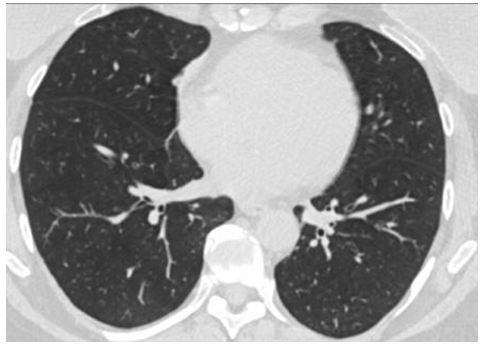

CO-RADS 1: Hình 1

Hình 1: CT phổi bình thường